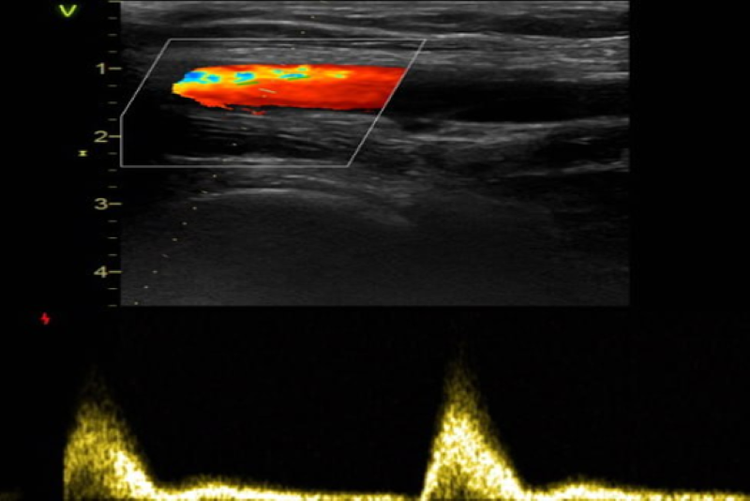

| Hình ảnh siêu âm phát hiện tình trạng huyết khối tĩnh mạch chày sau hai bên. Ảnh BVCC |

Bệnh nhân được bác sĩ chỉ định các kỹ thuật cận lâm sàng cần thiết phục vụ quá trình chẩn đoán. Trong đó, hình ảnh siêu âm mạch chi dưới phát hiện tình trạng huyết khối tĩnh mạch chày sau hai bên.

Bệnh nhân T. được chẩn đoán xác định huyết khối tĩnh mạch chày sau hai bên theo dõi do dùng thuốc tránh thai. Bác sĩ tiến hành kê đơn thuốc điều trị cho bệnh nhân và theo dõi sát sao tình hình sức khỏe.